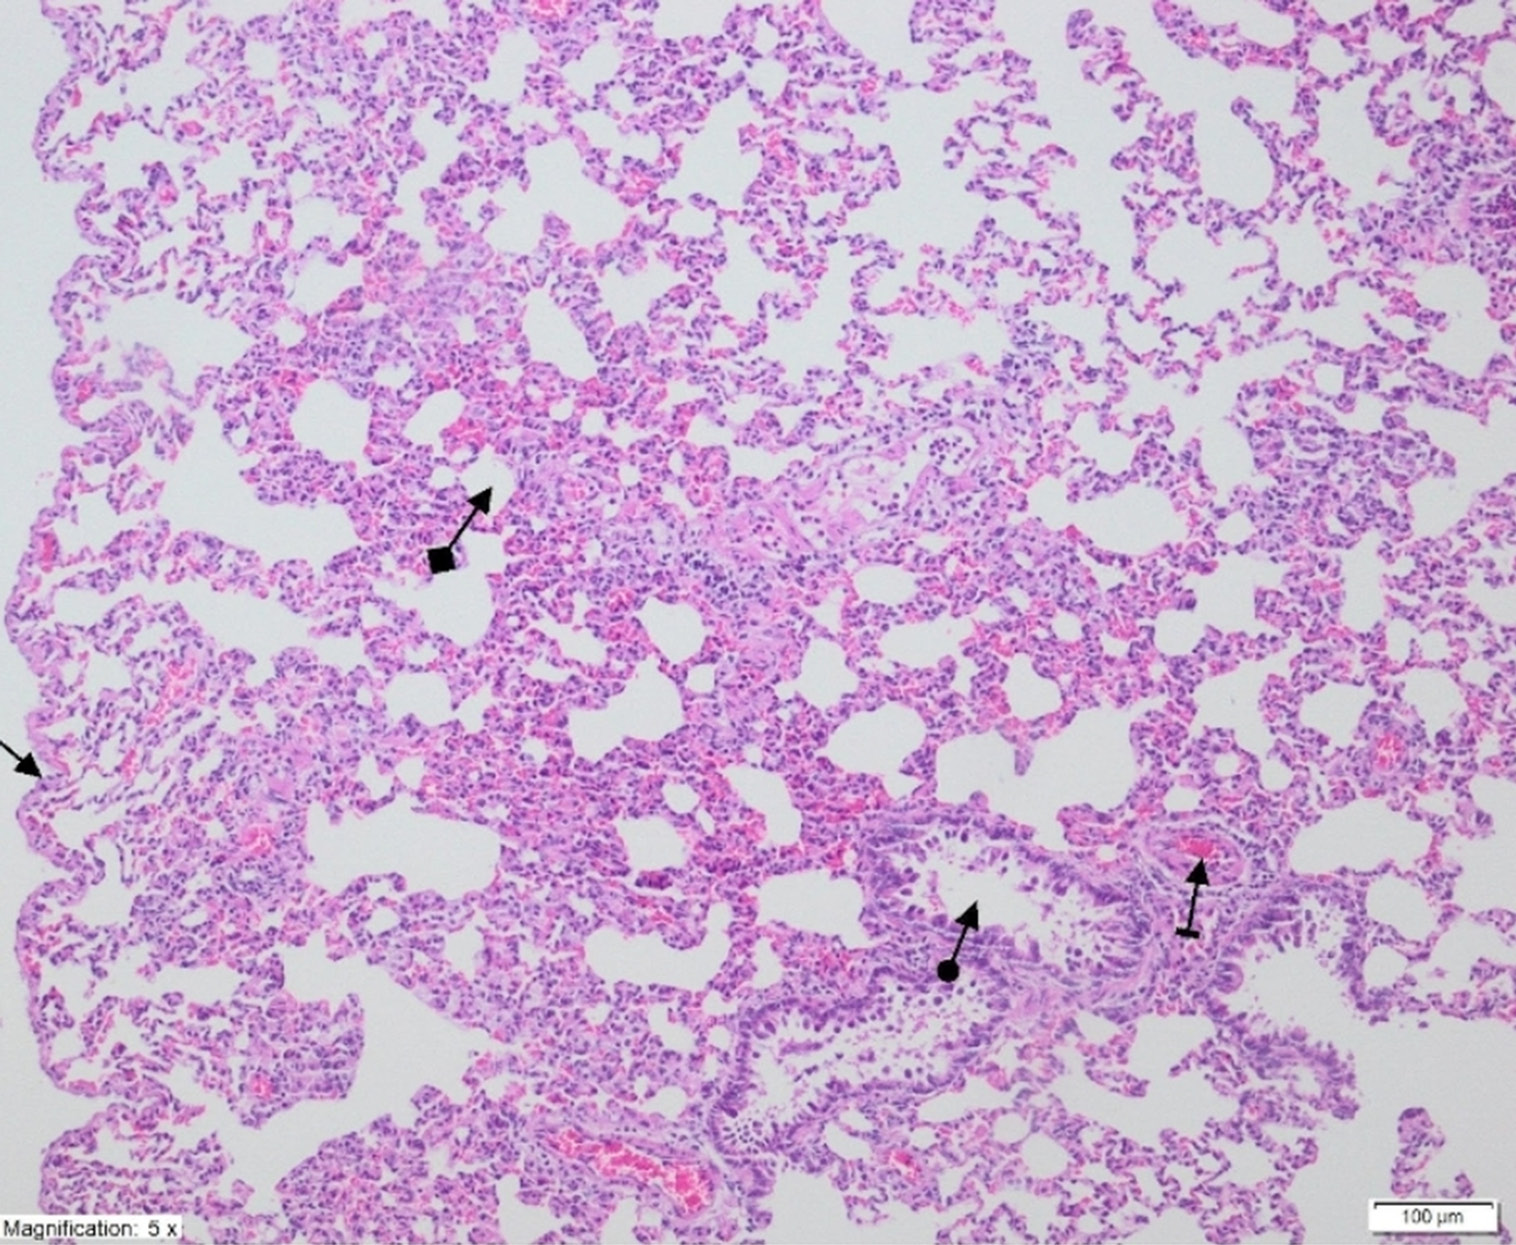

On histopathological examination, the alveolar vein, bronchiole structures and pleural mesothelium were identified as normal in pulmonary tissues in the SG group (Figure 4). However, significant areas of alveolar degeneration, edema and hemorrhage were observed in the pulmonary tissues of the LIR group (Figure 5). Congestion, PMNL and lymphocytic infiltration were observed in the lung tissues in the LIR group (Figure 6). In the lung tissue of the RLIR group, the pleural mesothelium, and alveolar, vascular and bronchial structures were identified as normal, which was similar to the observations in the SG group (Figure 7).